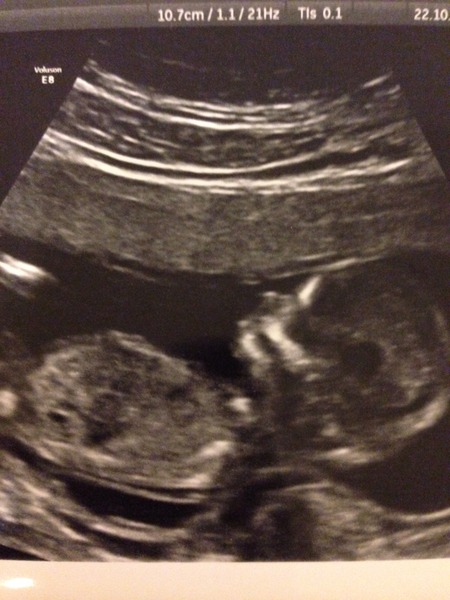

Hi all, the scan went ok yesterday. Turns out I'm slightly further along than I thought and due in April not May. Baby wouldn't stop wriggling and the nurse had a fair bit of trouble getting the measurements let alone some decent photos for us. We were only supposed to get 3 pictures but she ended up giving us 8 which was nice of her. It was really exciting once I was actually there, I hadn't realised how much it would be moving around and stuff already, we saw its mouth opening and closing and it kicked it's little feet and rolled over and wriggled about (away from the sonogram thing). DP was sooo happy.

GettheRedOut It's lovely to see that scan, I'm so glad it cheered you up and it'll be sure to encorage others.